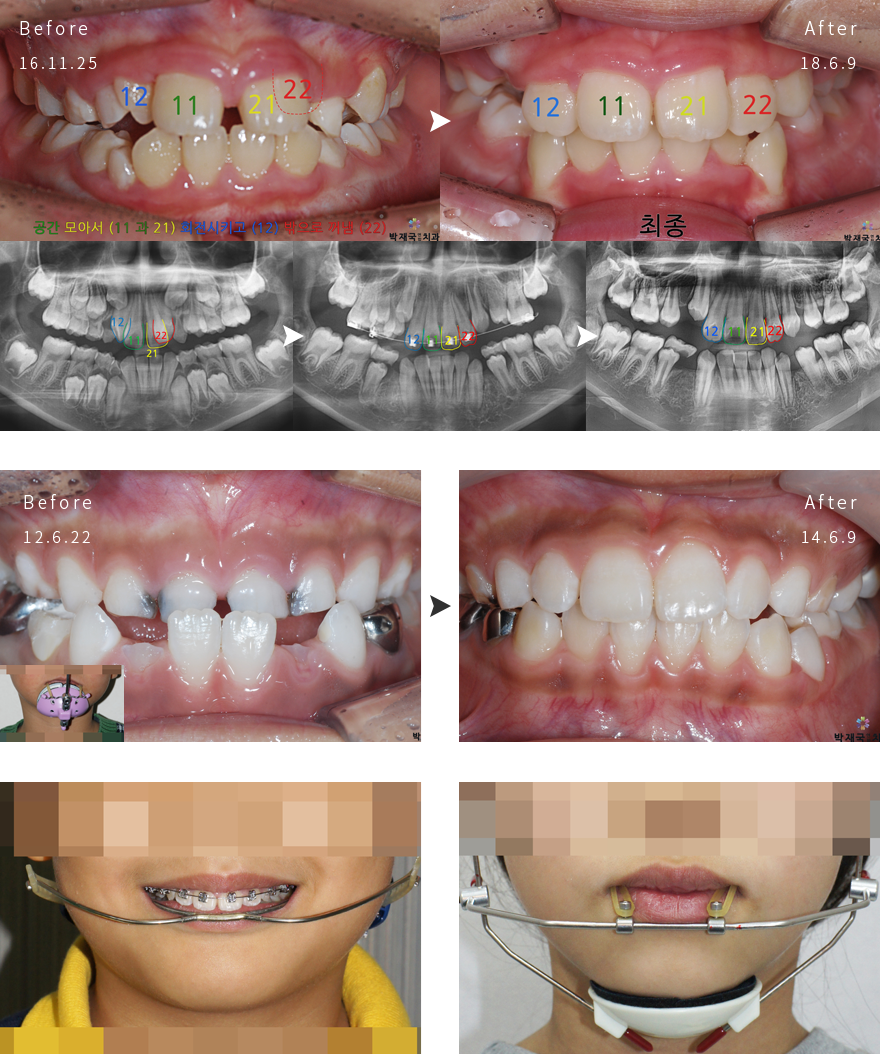

¾î¸°À̱³Á¤ »ç·Ê